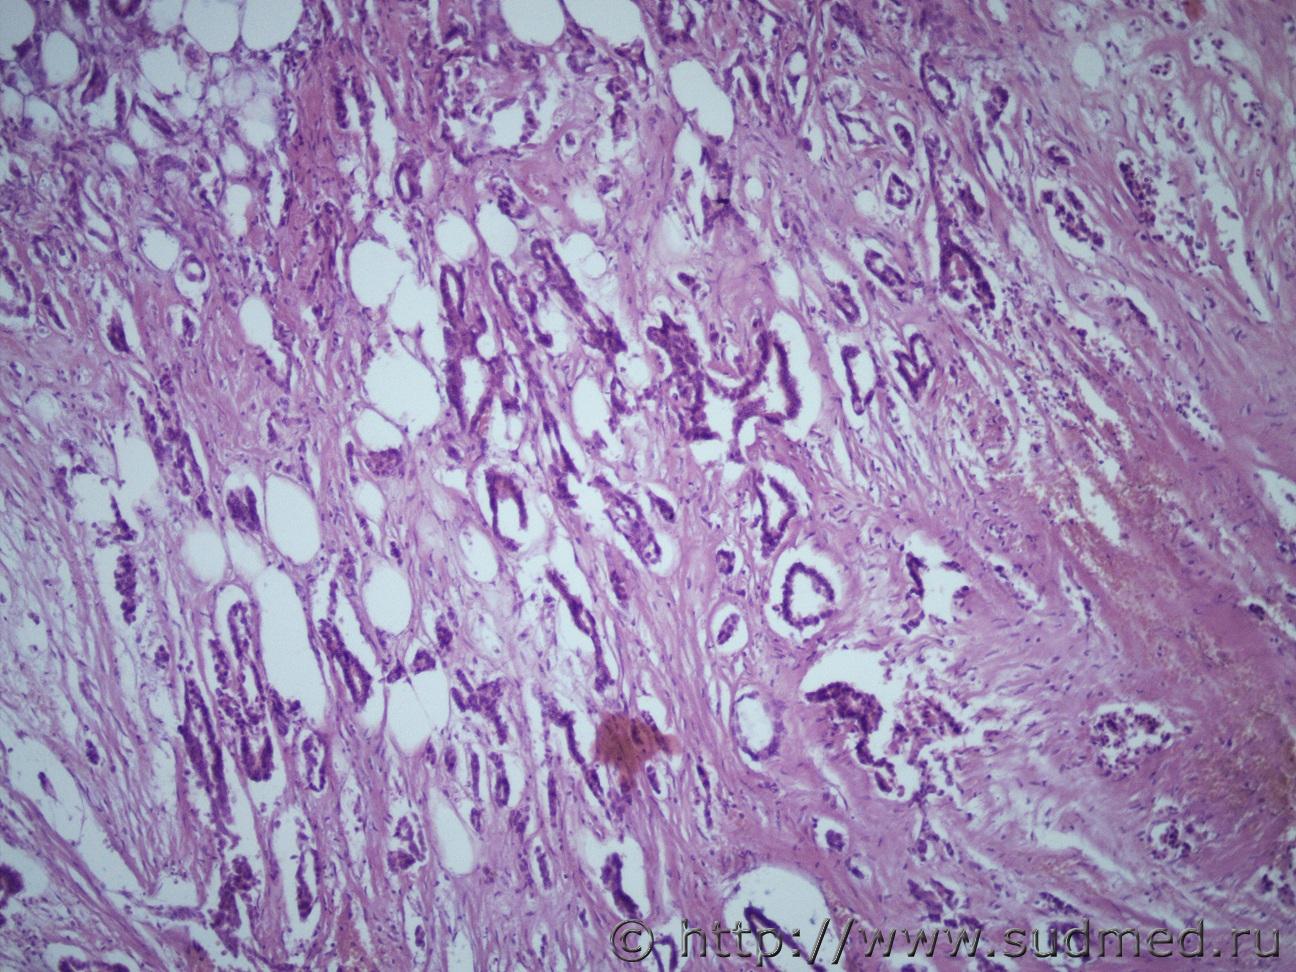

метастазы |

Ув. коллеги помогите))) Рак ПЖ с метастазами в брыжейку кишечника, забрюшинное пространство, большой сальник. Самой ПЖ на исследование не прислали. Есть только метастазы. Могу ли я по ним написать заключение, что это метастазы такого-то рака ПЖ? Микро-пролиферация атипичных полиморфных клеток с крупными и мелкими гиперхромными ядрами округлой, овальной, неправильной формы с патологическими митозами, напоминающими строение железистых структур. Мне кажется это протоковая аденокарцинома.